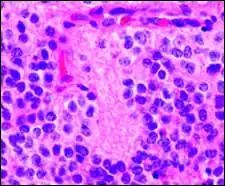

Гистопатологический образец нейробластомы с розетками Гомера Райта, окраска гематоксилин-эозин

Псевдорозетки Гомера Райта является одним из видов псевдорозеток, в котором дифференцированные клетки опухолей окружают нейропиль.[7] Примерами опухолей, содержащих эти розетки, являются нейробластома, медуллобластома, пинеалобластома и примитивные нейроэктодермальные опухоли кости. Розетки Гомера Райта являются «псевдо» в том смысле, что они не настоящие розетки. Настоящие розетки — это розетки Флекснера-Винтерштайнера, которые содержат пустой просвет. Розетки Гомера-Райта содержат большое количество фибриллярного материала. Они названы в честь Джеймса Гомера Райта.